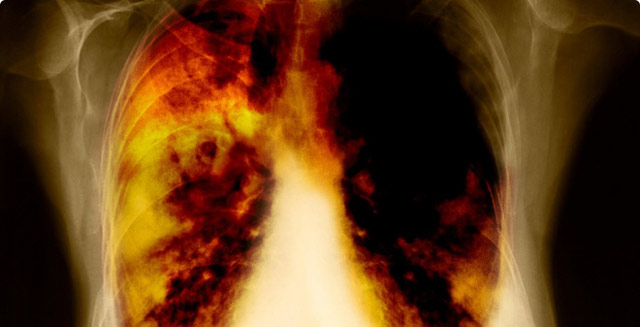

- Kỹ thuật chẩn đoán hình ảnh: siêu âm, chụp X quang, chụp cắt lớp vi tính,...